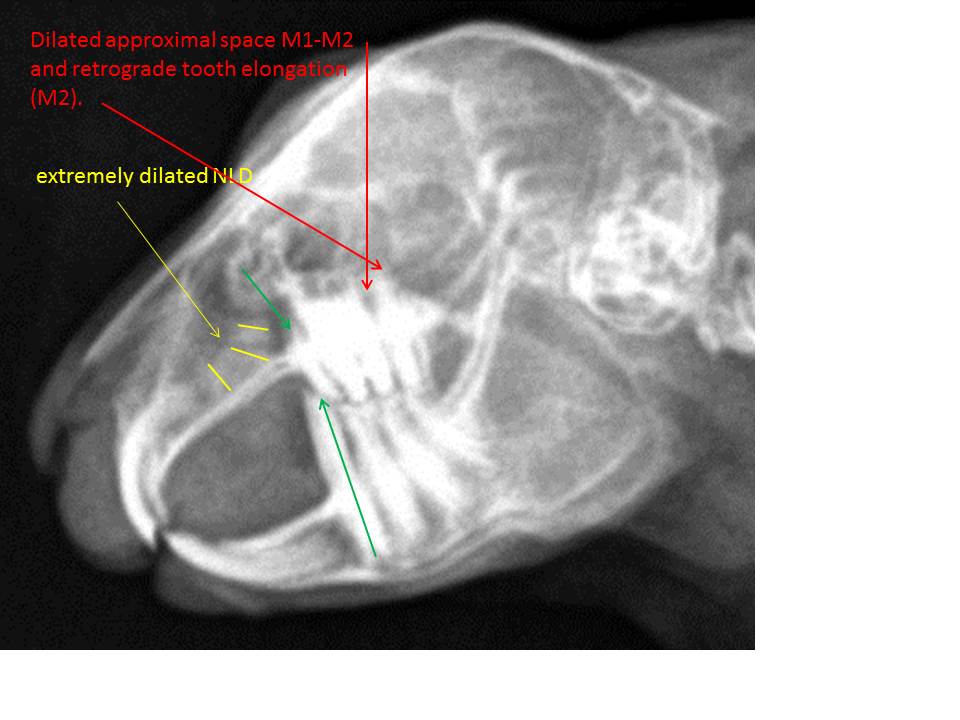

– the nasolacrimal duct is extremely dilated (yellow lines); uni- or bilateral? did you flush it? any clinical signs? chronic „snuffler?“

– the last but one upper cheek tooth (M2) shows an apex elongation (retrograde growth) and there is a widened approximal space M1-M2 (which side?) (red arrows). Since there is an abnormal radiodense structure visible within the caudal part of the right orbita on the dv-view (red arrow), we might be inclined to assume a retrobulbar infection or at least a retrograde elongation of the caudal cheek teeth with a possible additional tooth deviation. Albeit the dv-view is not positioned absolutely symmetrically, I think this area looks strange and therefore should be checked in more detail. The somehow „thickened“ and unphysiologically structured caudal part of the mandible (yellow arrows) might only be the result of the asymmetrical positioning? It’s really difficult to say. Dv-views can always be easier and much better interpreted, if the neck of the animal is slightly pressed down to the table. In doing so, you can also better validate the alveolus of the first maxillary cheek teeth (P2) (see the image top left for comparison). The apex/dental body of one or both (?) first upper cheek teeth appears to be abnormally short and maybe pointed ((green arrow on the lateral view). In my experience, the antagonists of similarly altered maxillary teeth tend to overgrow intraorally since they simply react to this mostly painful primary pathology of the maxillary premolar (P2). So also in this case, the first lower cheek tooth (P3) depicts an extreme elongation of its clinical crown (long green arrow) as a consequence of insufficient tooth wear due to the painful pathology of the first maxillary cheek tooth (P2) (green arrow). This is an indication for a more thorough examination of both upper premolars and the caudal molars (M1+M2). Therefore, I would inform the owner about these initial findings and recommend a more detailed dental check-up consisting of at least four standard skull views and an intraoral radiograph of the maxilla, additionally (using a flexible digital plate). Based on the new findings a targeted therapy can be planed. Since the radiodensity within the orbita can be the consequence of a primary mandibular pathology as well, I would take an intraoral radiograph of the mandibula, too. Another possible option is a CT study. It depends on the owner (costs).